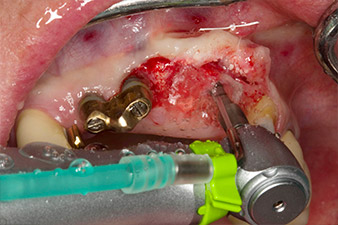

Une fois la cicatrisation primaire obtenue, les tissus mous ont été formés à l'aide du bridge doublé à la base. Deux mois plus tard, la zone a été exposée au moyen d'une incision de la crête alvéolaire légèrement orientée côté palatin (Fig 2). Les dimensions de l'os alvéolaire se sont avérées suffisantes en position 22. Les Figures 2 et 4 illustrent la préparation du lit implantaire, le taraudage et la pose de l'implant à l'aide de l'Implantmed.

Le nouveau moteur d'implantologie a été utilisé avec les contre-angles chirurgicaux de W&H correspondants.

WS-75 L suivant un ratio de 20:1 (programme P5).